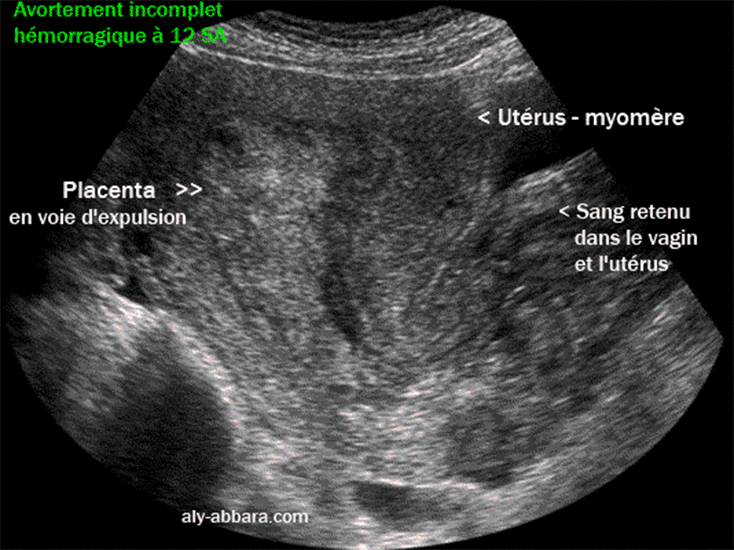

Avortement incomplet à 12 SA avec rétention complète du placenta

Image échographique montrant un avortement spontané incomplet à 12 SA

avec la rétention du placenta après avoir expulsé le fœtus.

Une important métrorragie avec des caillots retenus dans la cavité utérine et dans le vagin